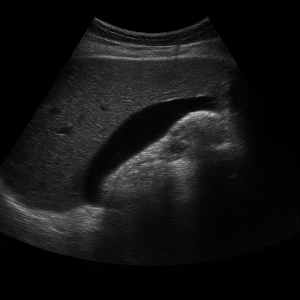

복부초음파는 우리 눈에 보이지 않는 높은 주파수의 소리(초음파)를 배 위에 대고 보내서, 몸속 장기와 혈관 구조를 실시간으로 영상으로 보는 검사입니다. 이 검사는 방사선을 사용하지 않고 통증이나 위험이 거의 없어, 안전하게 여러 번 반복할 수 있어요 .

초음파가 배 안 장기나 조직에 부딪히면 일부는 반사되어 돌아오고, 이 반사파를 탐촉자가 받아 전기 신호로 바꿔요. 컴퓨터가 이 신호를 이용해서 화면에 영상으로 보여줍니다 .

영상이 만들어지는 원리는 시간(반사파가 돌아오는 속도)과 강도(얼마나 세게 반사되었는지)를 컴퓨터가 계산해 이미지의 위치와 밝기를 결정하는 방식이에요. 깊이가 깊을수록 반사되는 시간도 길어지고, 반사파가 세면 화면에서 밝게 나타나요 .